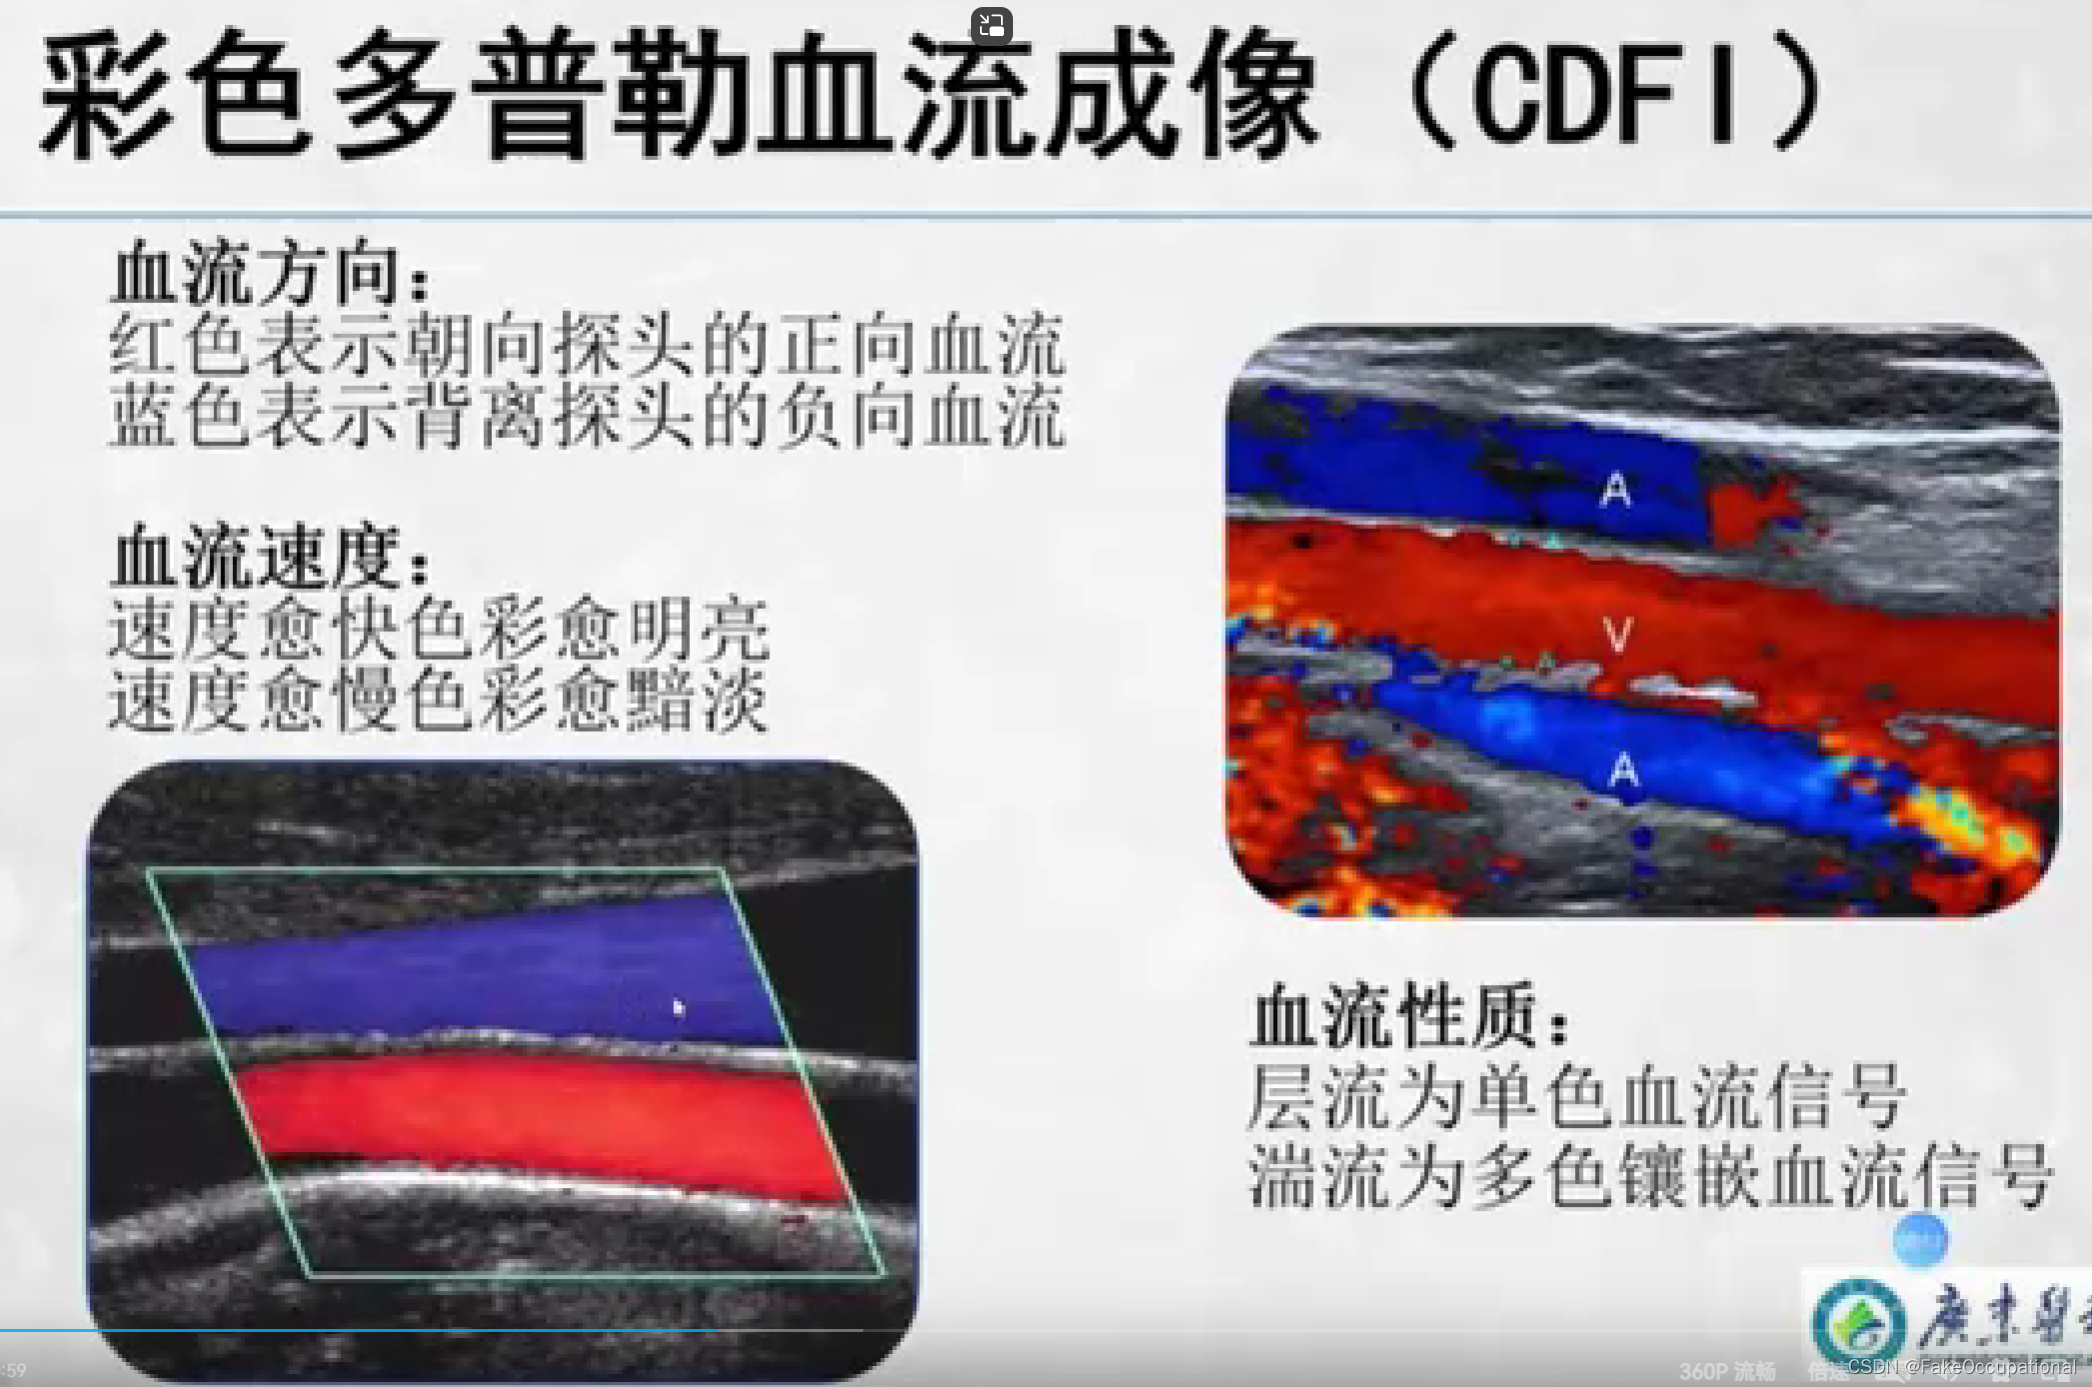

- 彩色编码实时显示血流方向、速度及血流性质:彩色多普勒血流成像(CDFI),彩色多普勒能量图(CDE)